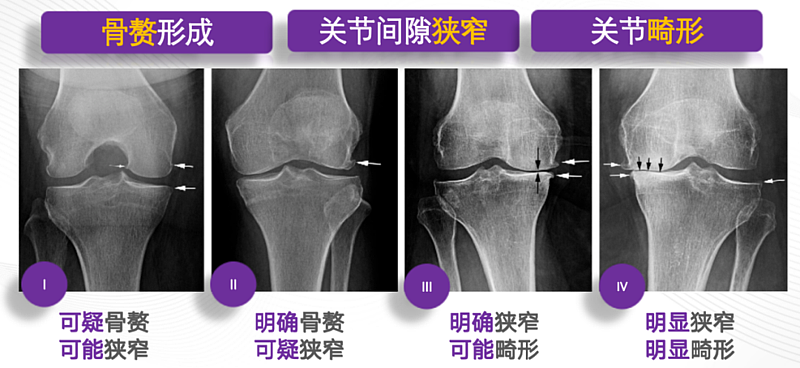

如下图所示,膝关节骨关节炎的进展与软骨磨损密切相关: